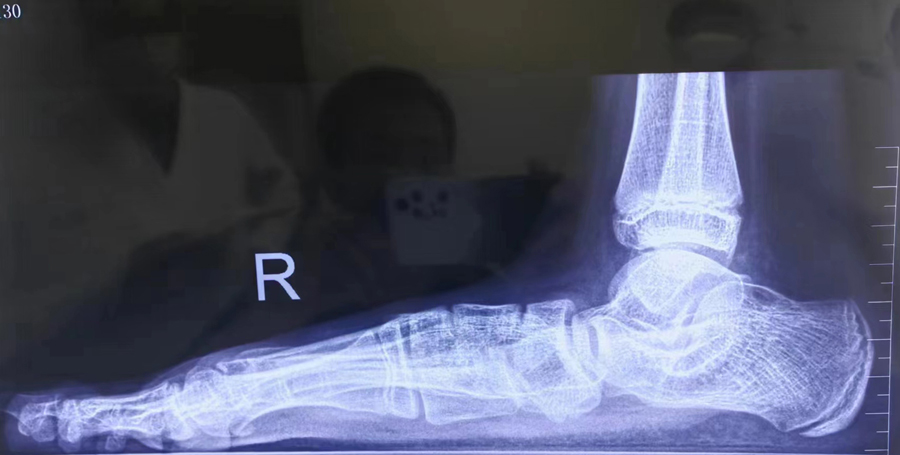

术前经过仔细查体及辅助检查评估,一套适合丹丹的手术方案制定好了——双侧跗骨窦螺钉植入距下关节制动术。

李浩教授介绍,距下关节制动术是指在跗骨窦处(脚踝附近)做一个长约1.5cm小切口,将跗骨窦螺钉(距下关节制动器)嵌入跗骨窦管腔内,以达到减小距下关节活动幅度、抬高足弓、纠正跟骨外翻的效果。距下关节制动术的优点在于创伤小、出血少、手术时间短、可早期下床活动、并发症少、疗效确切,能保留关节良好活动度。

李浩教授介绍,如果8周岁以上的儿童扁平足比较严重,经过足部力量锻炼、矫形鞋垫等保守治疗后还是有疲劳、疼痛等不适感,要考虑微创矫形手术治疗。手术年龄一般为8—12周岁,如果患儿病情严重,手术年龄可提前至6—7周岁。儿童扁平足的主要特征是足弓塌陷、跟骨外翻、内踝向内突出,家长可以尝试踩足印的方法来识别儿童扁平足,必要时,及时带孩子就诊,由临床专科医生通过查体、拍站立位负重X光片进行评估。